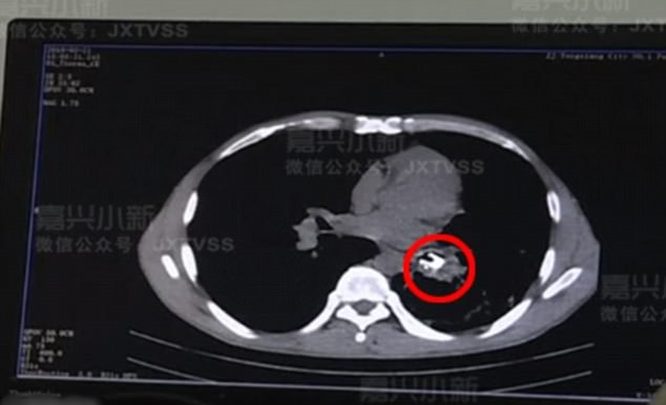

وقرر الطبيب المشرف على الحالة إجراء عملية جراحية بعد مسح تصوير مقطعي لـ”هاو”، ووجد ظلًا أبيض تحت الجزء السفلي الأيسر من القصبة الهوائية، قبل أن يتذكر “هاو” حادثًا غريبًا وقع في عام 1987، وأخبر الطبيب أن هذا الشيء يمكن أن يكون حامل المصباح الكهربائي.